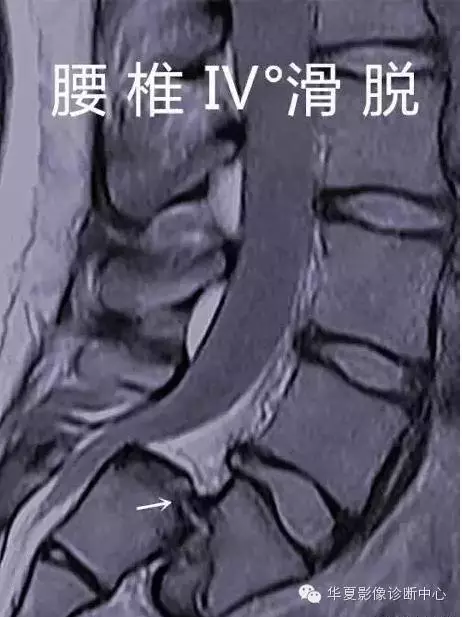

腰椎滑脫分度

椎體滑脫程度分級-Meyerding分級

將下位椎體上緣分為4等分,依據上位椎體對下位椎體向前滑移的程度分為4度:

- Ⅰ度:椎體向前滑移程度不超過椎體中部矢狀徑的1/4。

- Ⅱ度:椎體向前滑移程度超過椎體中部矢狀徑的1/4,但不超過2/4。

Ⅲ度:椎體向前滑移程度超過椎體中部矢狀徑的2/4,但不超過3/4。

V度:椎體向前滑移程度超過椎體中部狀徑的3/4。